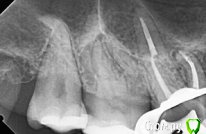

tatsiana.ma Опубликовано 3 сентября, 2017 Поделиться Опубликовано 3 сентября, 2017 Здравствуйте!Беспокоит 17 зуб, периодически возникает несильно выраженная боль, причем исключительно ночью. Врач сказал, что визуально не видит проблем. При такой симптоматике есть смысл снимать пломбу и смотреть на наличие вторичного кариеса? Боюсь дотянуть до пульпита, каналы не подарок, другую верхнюю семерку в своё время пришлось удалить, т.к. из-за сложной анатомии доп канал так и не смогли пройти.Снимки есть после лечения соседней шестерки. Ссылка на комментарий